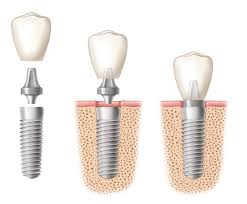

Faze ugradnje implantata

- Implantati se hirurški ugrađuju u kost. Postupak je brzo gotov i bezbolan, budući da se izvodi pod lokalnom anestezijom. Nakon ugradnje implant srasta sa kosti - “osteointegracija“ , što obično traje 2 do 6 meseci.

- Nakon ovog perioda na implant se postavlja nadgradnja (suprastruktura) na koju ide protetska krunica ili neko drugo protetsko resenje u zavisnosti od plana terapija.